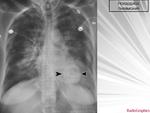

Двусторонняя интерстициальная. Гипертрофия правого корня, перисциссурит малой щели справа. Как бы не вылез центральный справа с лимфогенными метастазами.

В пользу лимфангита еще преимущественное распространение в средних и нижних отделах, неструктурные корни, еще cuffing (разбухание?) стенки бронхов, подчеркнутость междолевых щелей (на боковом хорошо видно, средняя доля "выделена")